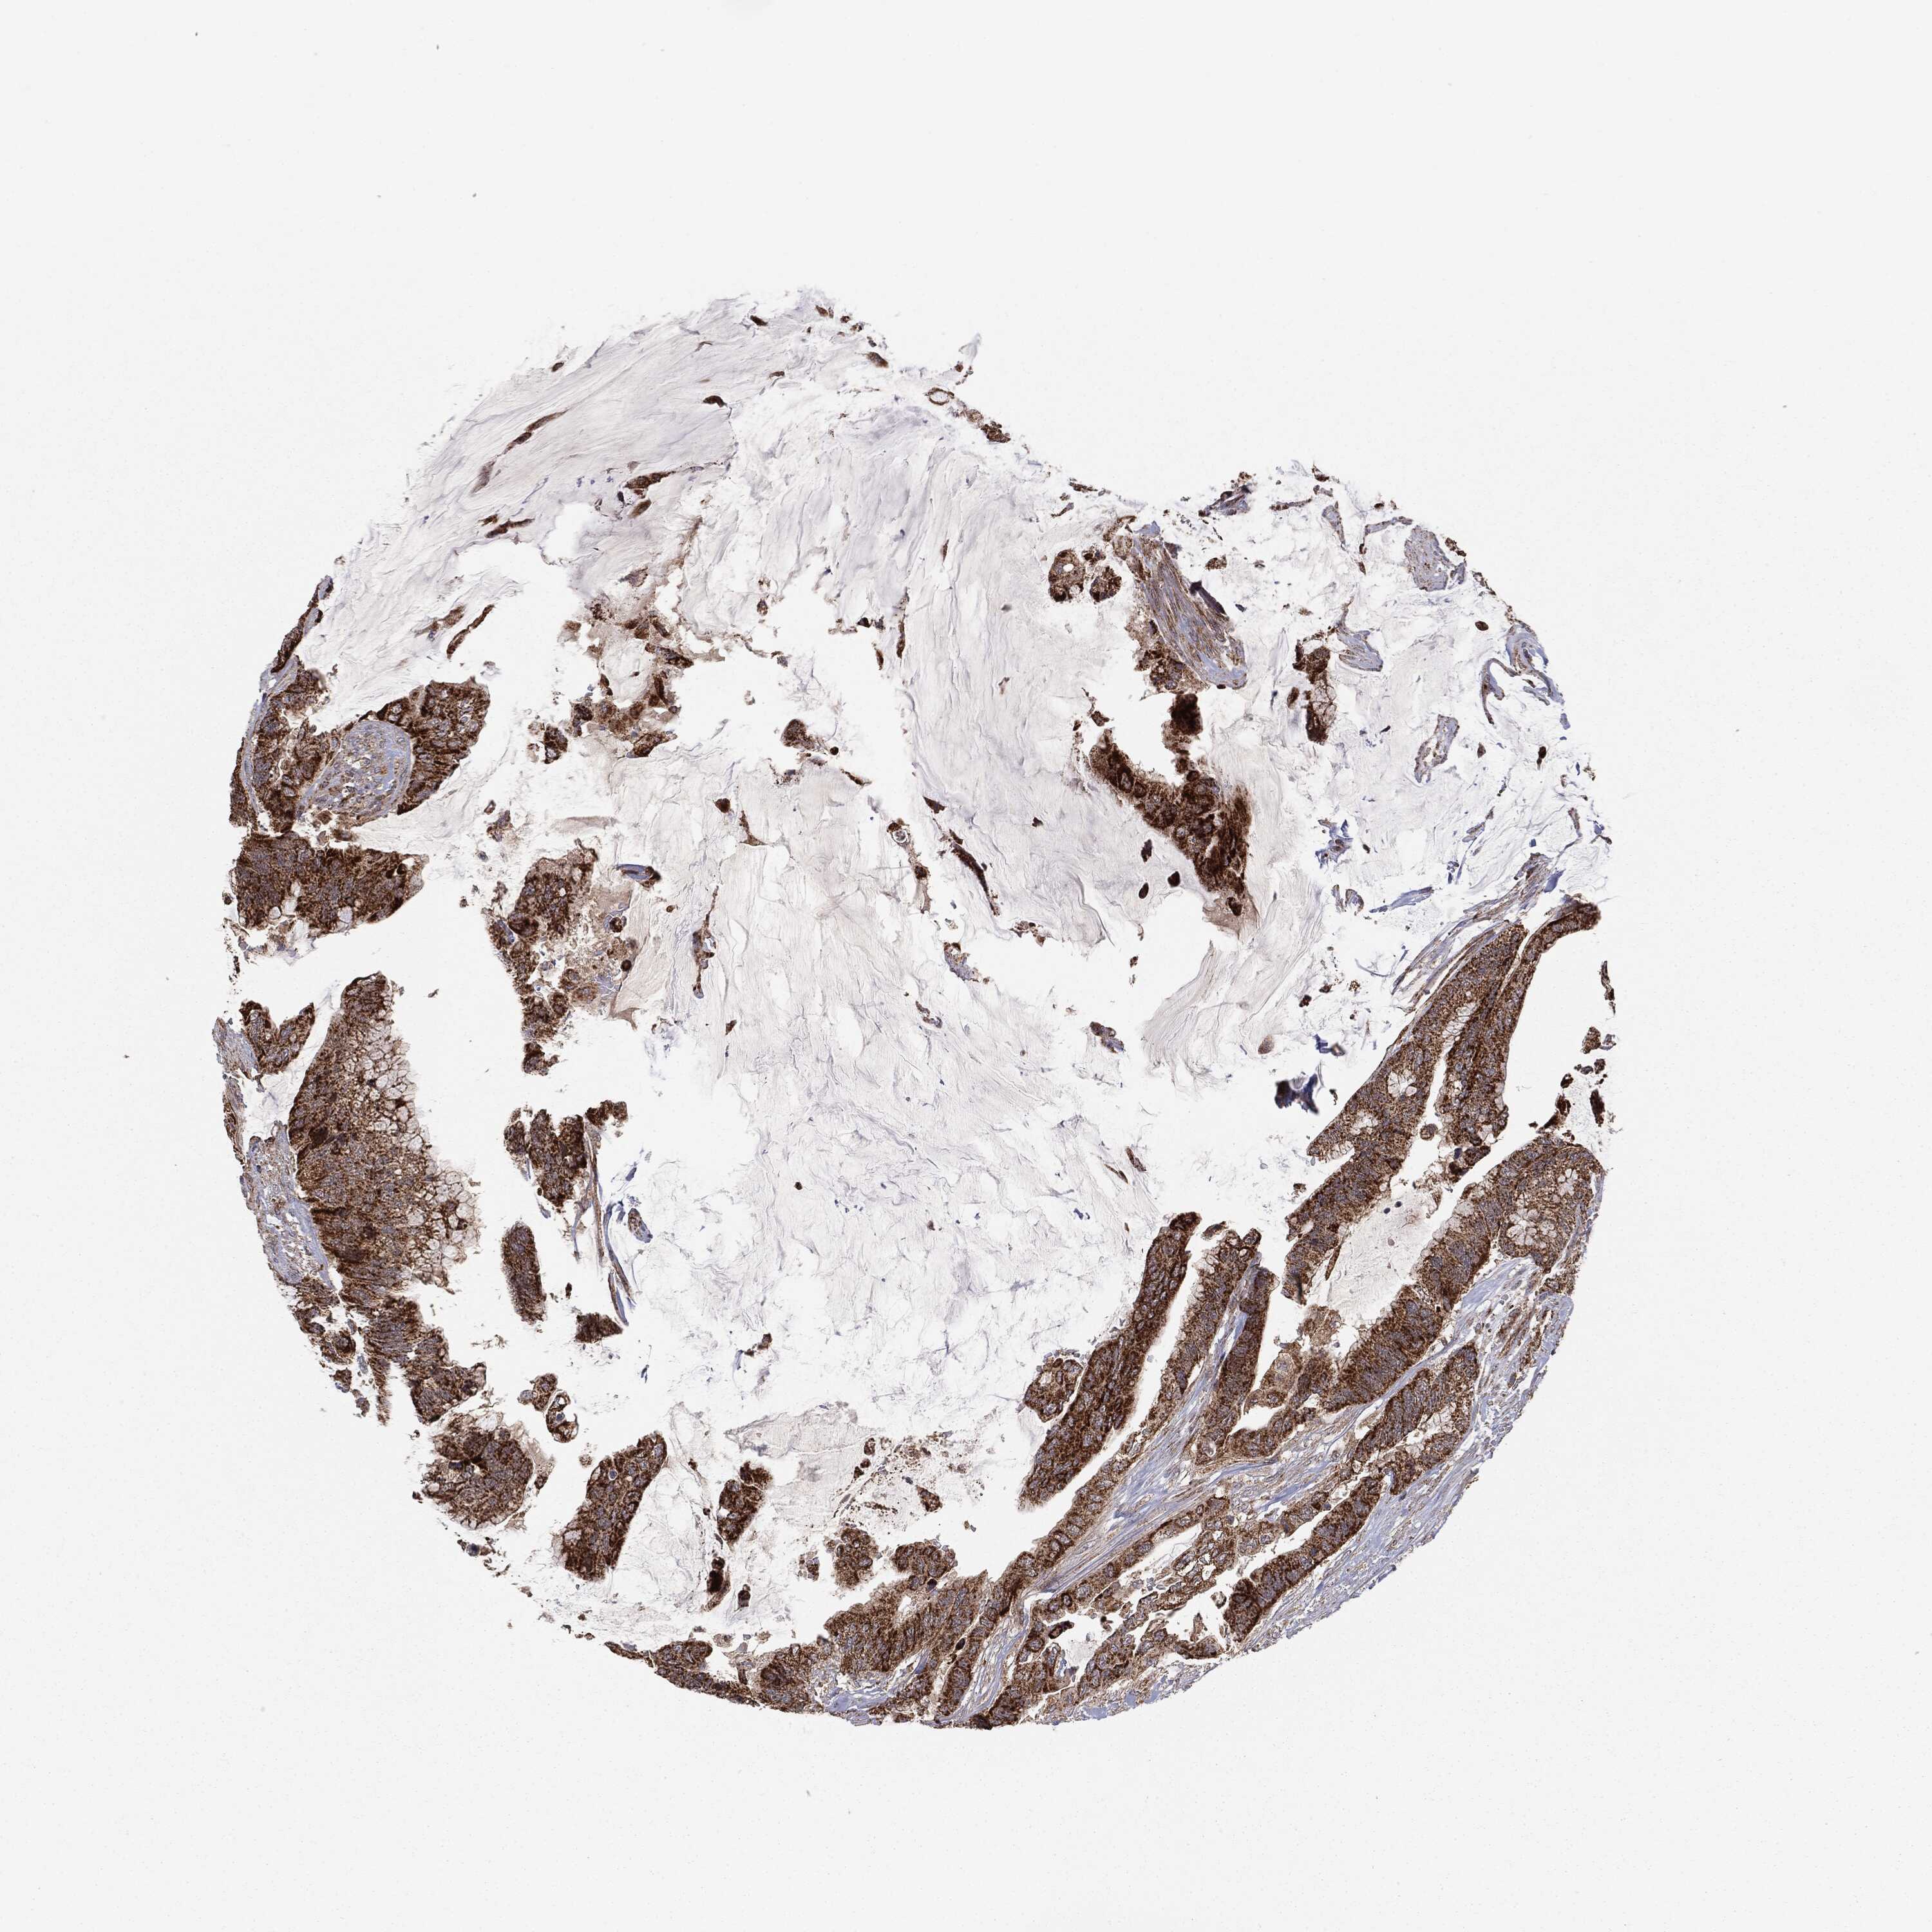

CANCER COLORECTAL CANCER Show tissue menu

Colorectal cancer

Human cancer

Colon adenocarcinoma